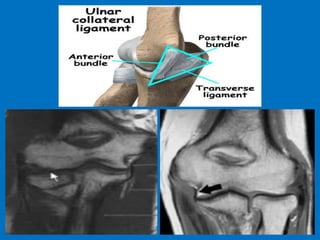

Ulnar collateral ligament (UCL) injury refers

to a sprain, partial tear or complete tear of

the ligament that traverses the inside (or

medial side) of the elbow. The UCL is the

primary stabilizer of the elbow and plays an

important role in throwing and hitting

sports, such as baseball, football and tennis.

Additional findings: Strain or rupture of the

common flexor tendon, ulnar neuropathy,

ulnar traction spurring or heterotopic

ossification of the soft tissues

and medial flexor insertion pronator tear.